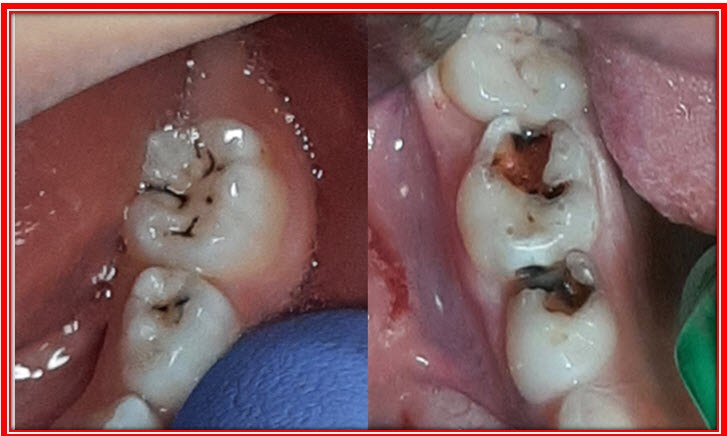

Sa kontinuiranom demineralizacijom zubna gleđ sve više slabi i u jednom trenutku puca stvarajući defekt na površini zuba koji se naziva kavitet (slika 1.).

Slika 1. Pucanje zuba (kavitet)